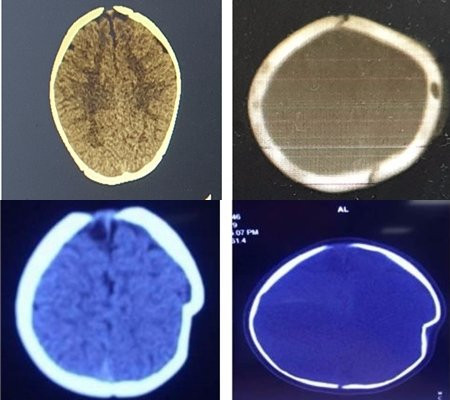

Kết quả kiểm tra cận lâm sàng, bệnh nhi được chẩn đoán lún sọ thái dương đỉnh trái 1cm. Để điều trị, bệnh nhi được chỉ định phẫu thuật.

Hình ảnh phim chụp sọ não bệnh nhi trước và sau khi phẫu thuật.